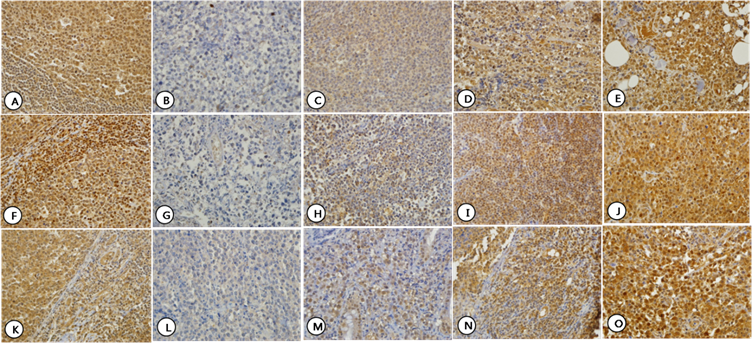

Expression patterns of HDAC4 (A-E), HDAC5 (F-J), and HDAC6 (K-O) which showed both nuclear and cytoplasmic staining. Normal lymphocytes in control tissue showed nuclear and cytoplasmic staining for HDAC4 (A), HDAC5 (F) and HDAC6 (K). For each HDAC, staining intensity was graded as Grade 0-3. Grade 0: HDAC4 (B), HDAC5 (G), and HDAC6 (L); Grade 1: HDAC4 (C), HDAC5 (H), and HDAC6 (M); Grade 2: HDAC4 (D), HDAC5 (I), and HDAC6 (N); and Grade 3: HDAC4 (E), HDAC5 (J), and HDAC6 (O).

HDAC1 was faintly expressed in the nucleus in normal lymph node tissue used as a control. In the cases studied, HDAC1 was expressed in nucleus in only 12 (13.2%) cases with faint staining intensity. HDAC1 staining was not observed in the cytoplasm (Fig. 1, A-C). HDAC2 was expressed exclusively in the nucleus both in control tissue and in the cases studied. High nuclear expression was found in 62 (68.1%) cases, and the remaining 29 (31.9%) cases showed low nuclear expression. HDAC2 staining was not observed in the cytoplasm (Fig. 1, D-H). HDAC4, 5, and 6 were expressed in both the nucleus and cytoplasm at varying intensities not only in control tissues but also in the cases studied. HDAC4 showed high expression in the nucleus and the cytoplasm in 34 (37.4%) and 56 (61.5%) cases, respectively, and low expression in the nucleus and the cytoplasm in 57 (62.6%) and 35 (38.5%) cases, respectively (Fig. 2, A-E). HDAC5 showed high expression in the nucleus and the cytoplasm in 73 (80.2%) and 53 (58.2%) cases, respectively, and low expression in the nucleus and the cytoplasm in 18 (19.8%) and 38 (41.8%) cases, respectively (Fig. 2, F-J). HDAC6 showed high expression in the nucleus and the cytoplasm in 37 (40.7%) and 81 (89.0%) cases, respectively, and low expression in the nucleus and the cytoplasm in 54 (59.3%) and 10 (11.0%) cases, respectively (Fig. 2, K-O). In general, HDAC4 showed similar patterns of expression pattern in the nucleus and cytoplasm, but HDAC5 and HDAC6 were preferentially expressed in the nucleus and cytoplasm, respectively (Table 2).